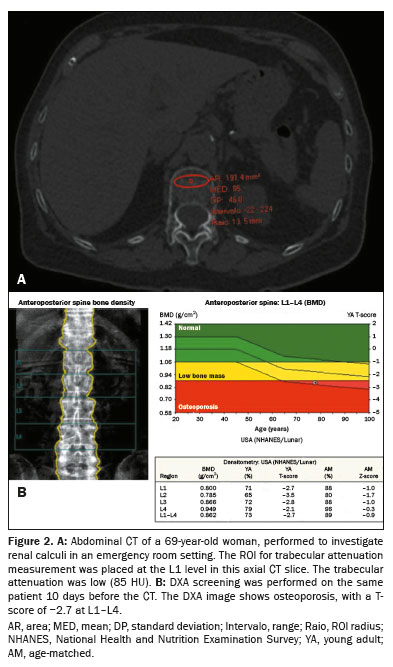

Each CT examination included the L1 trabecular space. Vertebral assessment on CT was performed by the evaluators on a standard picture archiving and communication system workstation; the images were viewed with the bone window settings routinely employed at our institution. A single ROI measuring 100–300 mm2 was placed within the trabecular bone of L1 in the transverse (axial) series to assess mean attenuation values(20–22). No angulation was required. In all cases, structures that could alter the ROI value, such as artifacts or vessels, were avoided (Figures 1 and 2).

For image acquisition and attenuation analysis, we employed multidetector CT scanners with 40, 80, or 320 detector rows, following standard institutional protocols. We measured trabecular attenuation at L1 in a standardized oval region of interest (ROI) of 100–300 mm2 on axial slices, avoiding cortical bone and vascular structures. Values > 160 HU were classified as normal, whereas those < 100 HU were considered indicative of osteoporosis(17). Unenhanced and contrast-enhanced CT scans were included. The specific models utilized were the Biograph mCT (Siemens Healthcare, Erlangen, Germany), Aquilion Prime (Canon Medical Systems, Tochigi, Japan), and Aquilion ONE (Canon Medical Systems). The scanning parameters adhered to institutional protocols, with scans being acquired when the patient was in the supine position and during end-inspiration. Contrast material was administered intravenously as needed. The reconstructed slice thickness was set at 1 mm, with a tube voltage of 80–120 kVp and an automatically modulated tube current of 10–440 mA. The CT scans were acquired in outpatients, inpatients, and emergency room patients; in the last two cases, the scans were always acquired at admission.

DXA

All of the DXA examinations performed at our institution comply with the regulations established by Brazilian national organizations, and all of the equipment employed undergoes regular maintenance. The DXA analysis was performed with a fan-beam densitometer (iDXA; GE Healthcare, Madison, WI, USA). We categorized bone quality on the basis of the T-scores, applying the World Health Organization criteria(22): normal (≥ −1), osteopenia (−1 to −2.5), and osteoporosis (< −2.5). All DXA examinations were conducted in outpatients.